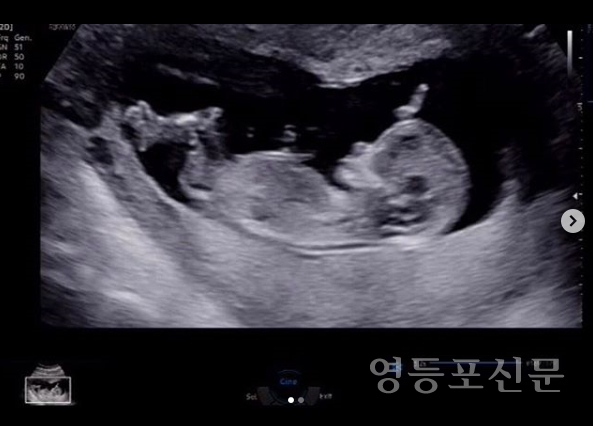

그는 1일 초음파 사진을 공개하면서 “골든이. 사랑하고 축복해. 우리 골든이 축복해주셔서 감사합니다”라고 밝혔다.

김영은은 5일 “골든이는 아들. 배가 뭉쳐서 1주일 만에 다시 찾은 병원. 이 녀석 엄마한테 너의 존재감을 알리려고 그런 거니? 왠지 아빠 판박이로 태어날 거 같구나”라고 남겼다.